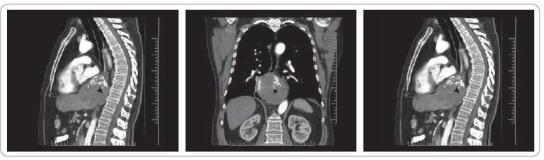

Pacient 1943, s kulovitým tumorem o průměru 15 cm distálního jícnu s metastázou do jater S3 6 cm a v.s. drobnými v ostatním jaterním parenchymu. Histologická diagnóza, GIST c-kit pozitivní, stanovena v dubnu 2008 v Ostravě. PET aktivita v místě tumoru a mírně jen S 3 jater. Pacient předán do léčby na MOÚ. Od května 2008 na biologické terapii - Glivec 400 mg tbl 1D. 9/2008 regrese tumoru o 30 %, PET aktivita následně jen v oblasti tumoru. 12/2008-6/2011 SD. 12/2011 přes terapii progrese velikosti tumoru s exulcerací sliznice distálního jícnu, krvácení s anemizací. Navýšení dávky Glivecu na 800 mg/D. 3/20012 konzultace chirurgického pracoviště, indikován k operační revizi. Pacient operován 2. 4. 2012 z levostranné torakofrenolaparotomie. Náhrada jícnu tubulizovaným žaludkem, anastomóza semimechanicky modo Orringer. Současně provedena i resekce jaterní metastázy S3. Výkon i pooperační období bez komplikací. Od šestého pooperačního dne dietní zátěž. Rána zahojena per primam. Hospitalizace 10 dnů. Pacient letos v lednu 2013 rehospitalizovaný na MOÚ pro MTS jaterní S7 13 mm a S8 14 mm. Provedena ablativní stereotaktická RT, 5 dávek, dále udržovací terapie Glivec 400 mg 1/D. Lokálně bez známky recidivy, bez polykacích či jiných potíží, s odstupem plánovaná kontrolní vyšetření - CT.